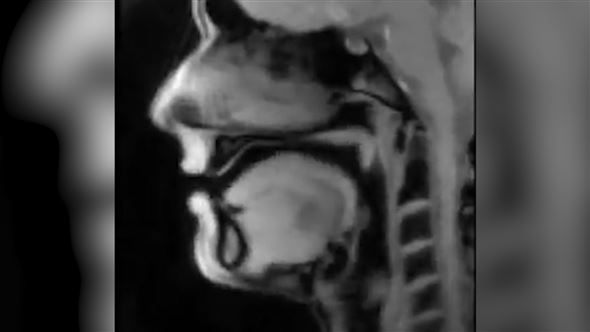

Der Göttinger Physiker Jens Frahm ist für sein bahnbrechendes Echtzeit-MRT bekannt. Mit jahrelanger Forschung ist es ihm gelungen, das herkömmliche MRT auf das bis zu 10.000-fache zu beschleunigen und so die inneren Körperfunktionen in Echtzeit zu filmen.